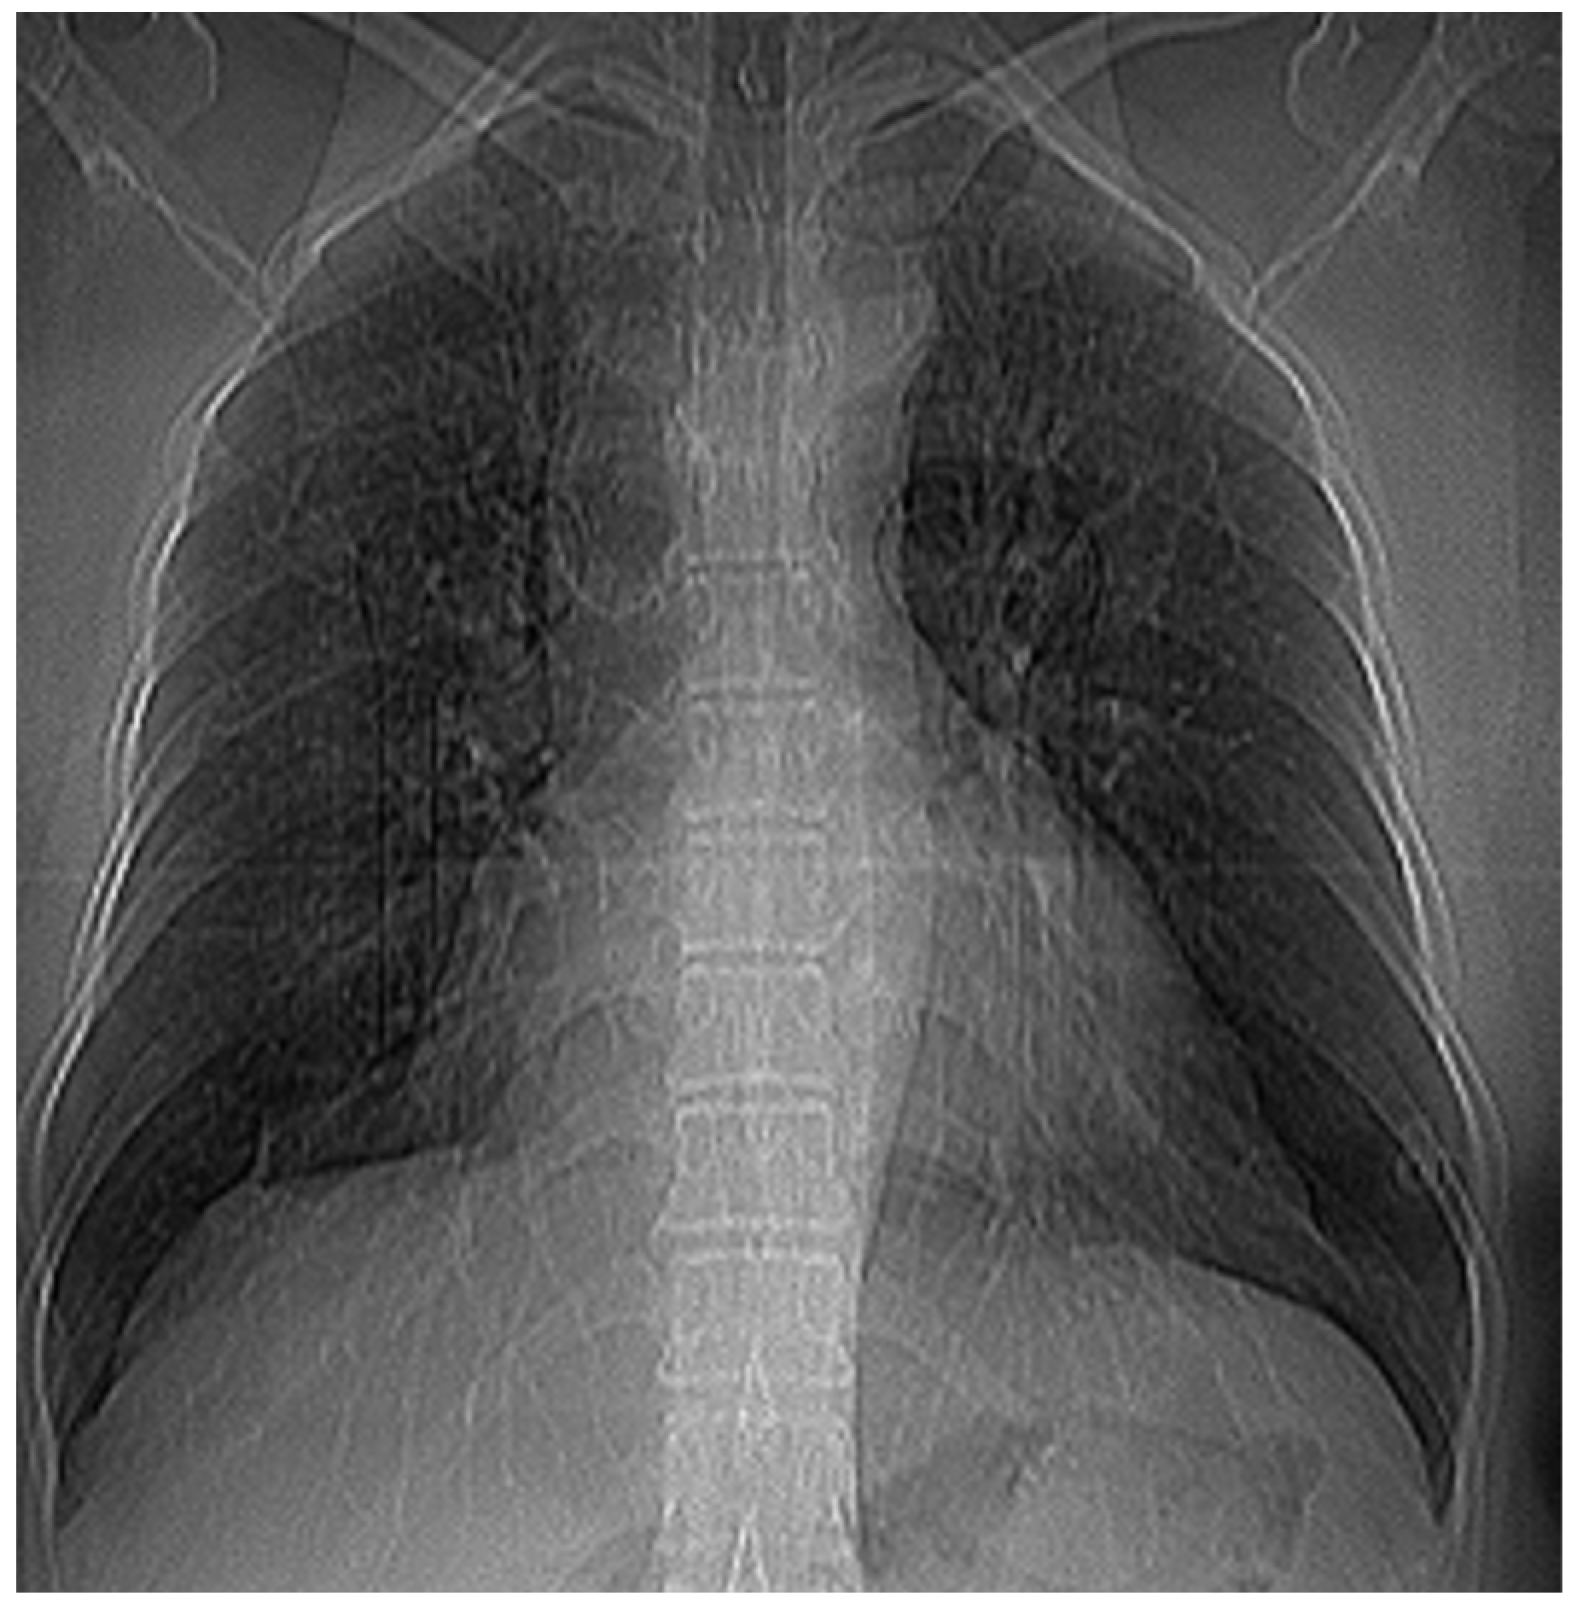

Figure 7 and Figure 8 show the selection of the lung portion of interest for the patient EF and the same image in “Invert color” format.

Figure 7. Selecting the portion of interest of the lungs of patient EF.

Fractalfract 07 00285 g007

Figure 8. The image from Figure 7 in “Invert color” format.

Fractalfract 07 00285 g008